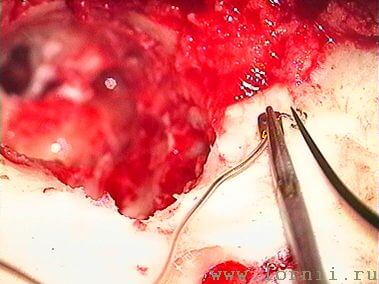

Затем борами подготавливали ложе, устанавливали и фиксировали в ложе имплант (рис. 9, 10). Соединительный кабель проводился через заднюю тимпаностому в барабанную полость.

У пациентов с аномалией развития уха и после радикальной операции катушка импланта была установлена в круглое окно (рис. 13, 15, 16). Для этого крепление катушки подворачивали (рис. 14). Далее укладывали фасцию височной мышцы в нишу окна улитки (рис. 15), затем на фасцию устанавливали катушку импланта и подворачивали края фасции. Фиксация конструкции обеспечивалась полоской аутохряща из ушной раковины пациентки (рис. 16).